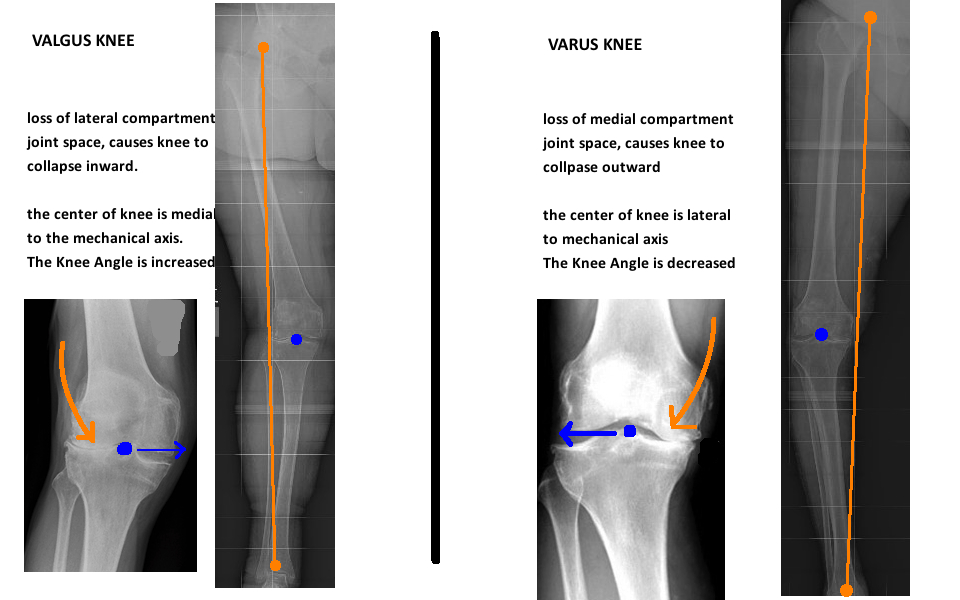

이러한 측정을 바탕으로 무릎의 상태를 표시하게 되는 데, 외전 및 내전된 슬관절을 가장 많이 표현하게 됩니다.

관절선 합체각(Joint Line Convergence Angle, JLCA) 은 한 관절의 두 개의 관절 방향선이 이루는 각도로 0~2도 가 정상입니다.